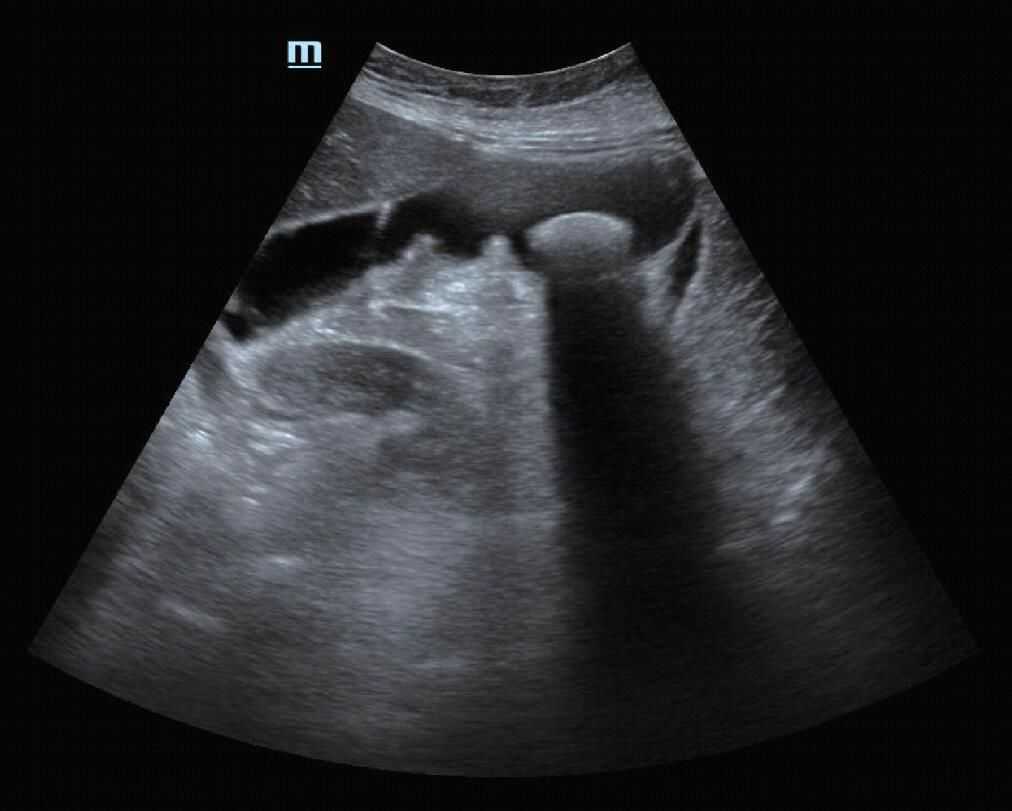

(7)后方回声增强:由于时间增益补偿(TGC)对于同等深度声衰减较小的目标进行作用时,目标后方回声增强的现象。后方回声增强效应对鉴别液性与实性病变有帮助(图12)。

图12囊肿后方回声增强